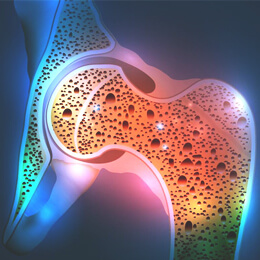

A csont a gerincesek vázrendszerét alkotó kemény szerv. A csontok szerkezetét ásványi anyagokkal (kalcium és foszfor) erősített csontszövet alkotja. A csontrendszer az emberi test súlyának hozzávetőlegesen 10%-át teszi ki. A speciális méhsejtszerű mátrixuknak köszönhetően a csontok merevek és szilárdak, miközben könnyűek is maradnak, ezzel is segítve a mozgást. A csontok nemcsak formát adnak testünknek és védelmet nyújtanak szerveinknek, hanem vörös- és fehérvérsejteket is termelnek, ásványi anyagok, így kalcium és foszfor raktáraként szolgálnak, valamint segítik a vér sav-bázis egyensúlyának szabályozását.

A csontszövet speciális rugalmas mátrixból (a csont ~30%) és kötött ásványi anyagokból (~70%) felépülő kemény kötőszövet, amelynek felépítését és lebontását speciális csontsejtek (osteoblastok és osteroclastok) végzik. A csontszövet ásványi anyagokkal megerősített, ún. mineralizált mátrixa főként a csontok rugalmasságát adó kollagénből és a merevséget biztosító szervetlen ásványi összetevőkből áll. Az emberi csont szárazanyag tartalmának kb. 65%-át kitevő szervetlen komponensek közül a legfontosabb a hidroxiapatit, a kalcium-karbonát, a magnézium-karbonát és a szilícium-dioxid. A mátrix pontos összetétele idővel változhat a táplálkozás és az öregedéssel összefüggő csontok ásványianyag-vesztése miatt.

A csontok egészsége a csontok erősségére és a csontszerkezet minőségére utal. A csontok egészségét általában csont ásványi sűrűségben mérik. A csontok egészségét többek között a tápanyagbevitel, a hormonális szabályozás, a testmozgás és az életkor is befolyásolja.